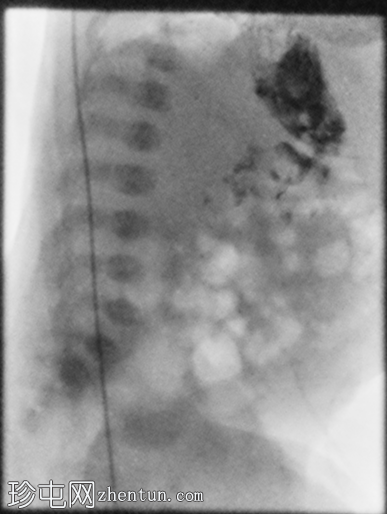

2.png

正位

胃部初始显影,并立即反流至食管裂孔疝。在其近端可见管径正常的远端食管。十二指肠降部和横部显影较弱,左上腹可见数段管径较小/部分减压的近端小肠显影。